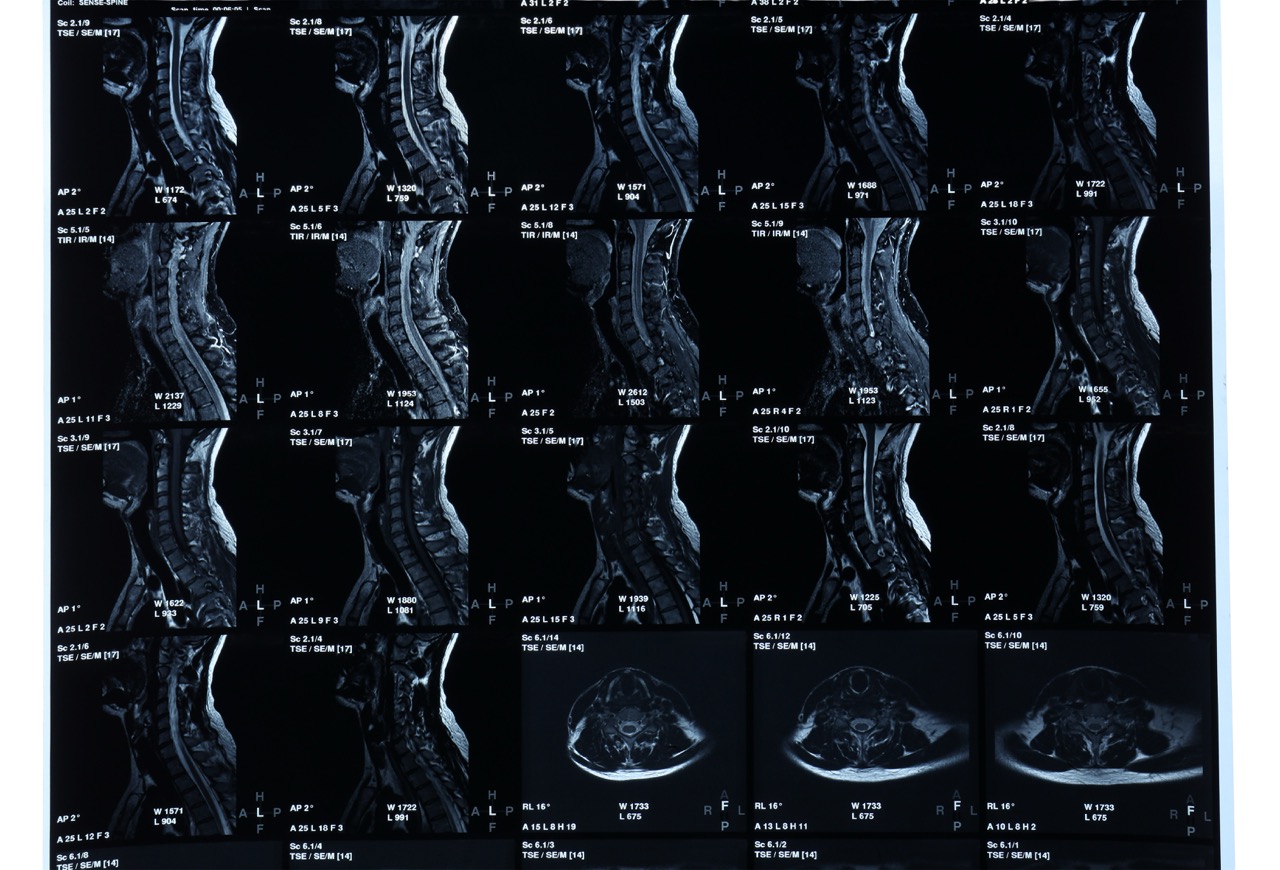

The GE HiField 1.5 Tesla MRI system is an advanced technology in medical imaging, providing high-resolution images for precise diagnoses. With innovative imaging sequences and software, it excels in neuroimaging, musculoskeletal imaging, and abdominal imaging. Patients benefit from shorter scan times and increased comfort, while healthcare providers rely on accurate diagnostic information for effective treatment planning.

Tesla MRI systems, available in strengths such as 1.5 Tesla and 3 Tesla, redefine medical imaging with unmatched clarity. Higher strengths, like 3 Tesla, deliver even sharper images, crucial for detecting subtle abnormalities. Widely applied in oncology, cardiology, and functional imaging, Tesla MRI assists clinicians in offering precise diagnoses and tailored treatments.

Understanding Your Cervical MRI Scan: What Every Patient Should Know Neck pain can be more than a daily discomfort, it